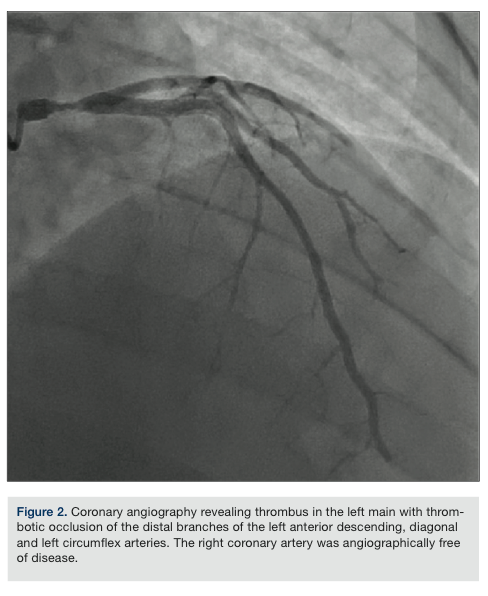

Given his initial presentation, despite the absence of significant risk factors for coronary disease, he was emergently taken up for cardiac catheterization. Angiography revealed a large thrombus in the large-caliber distal left main coronary artery (LM) and smaller thrombi were noted in the distal left anterior descending (LAD), mid diagonal branch of the LAD, and distal left circumflex artery (LCx) (Figure 2). The distal thrombi were thought to be embolic fragments from the large thrombus in the LM coronary artery. The right coronary artery was

dominant and its branches were angiographically free of disease.